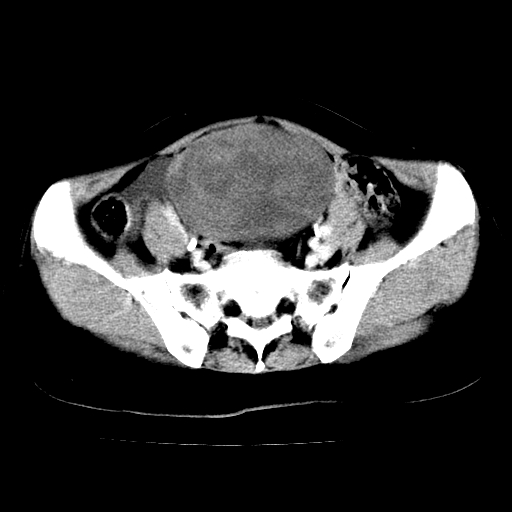

标题: CT24785:女,62岁,发现下腹部肿物半年。 [打印本页]

女,62岁,发现下腹部肿物半年,下腹部不适。

老年女性患者,盆腔囊实性占位,ct增强不均匀强化,未见壁结节,未见腹水及盆腔积液,考虑附件囊腺瘤可能性大!